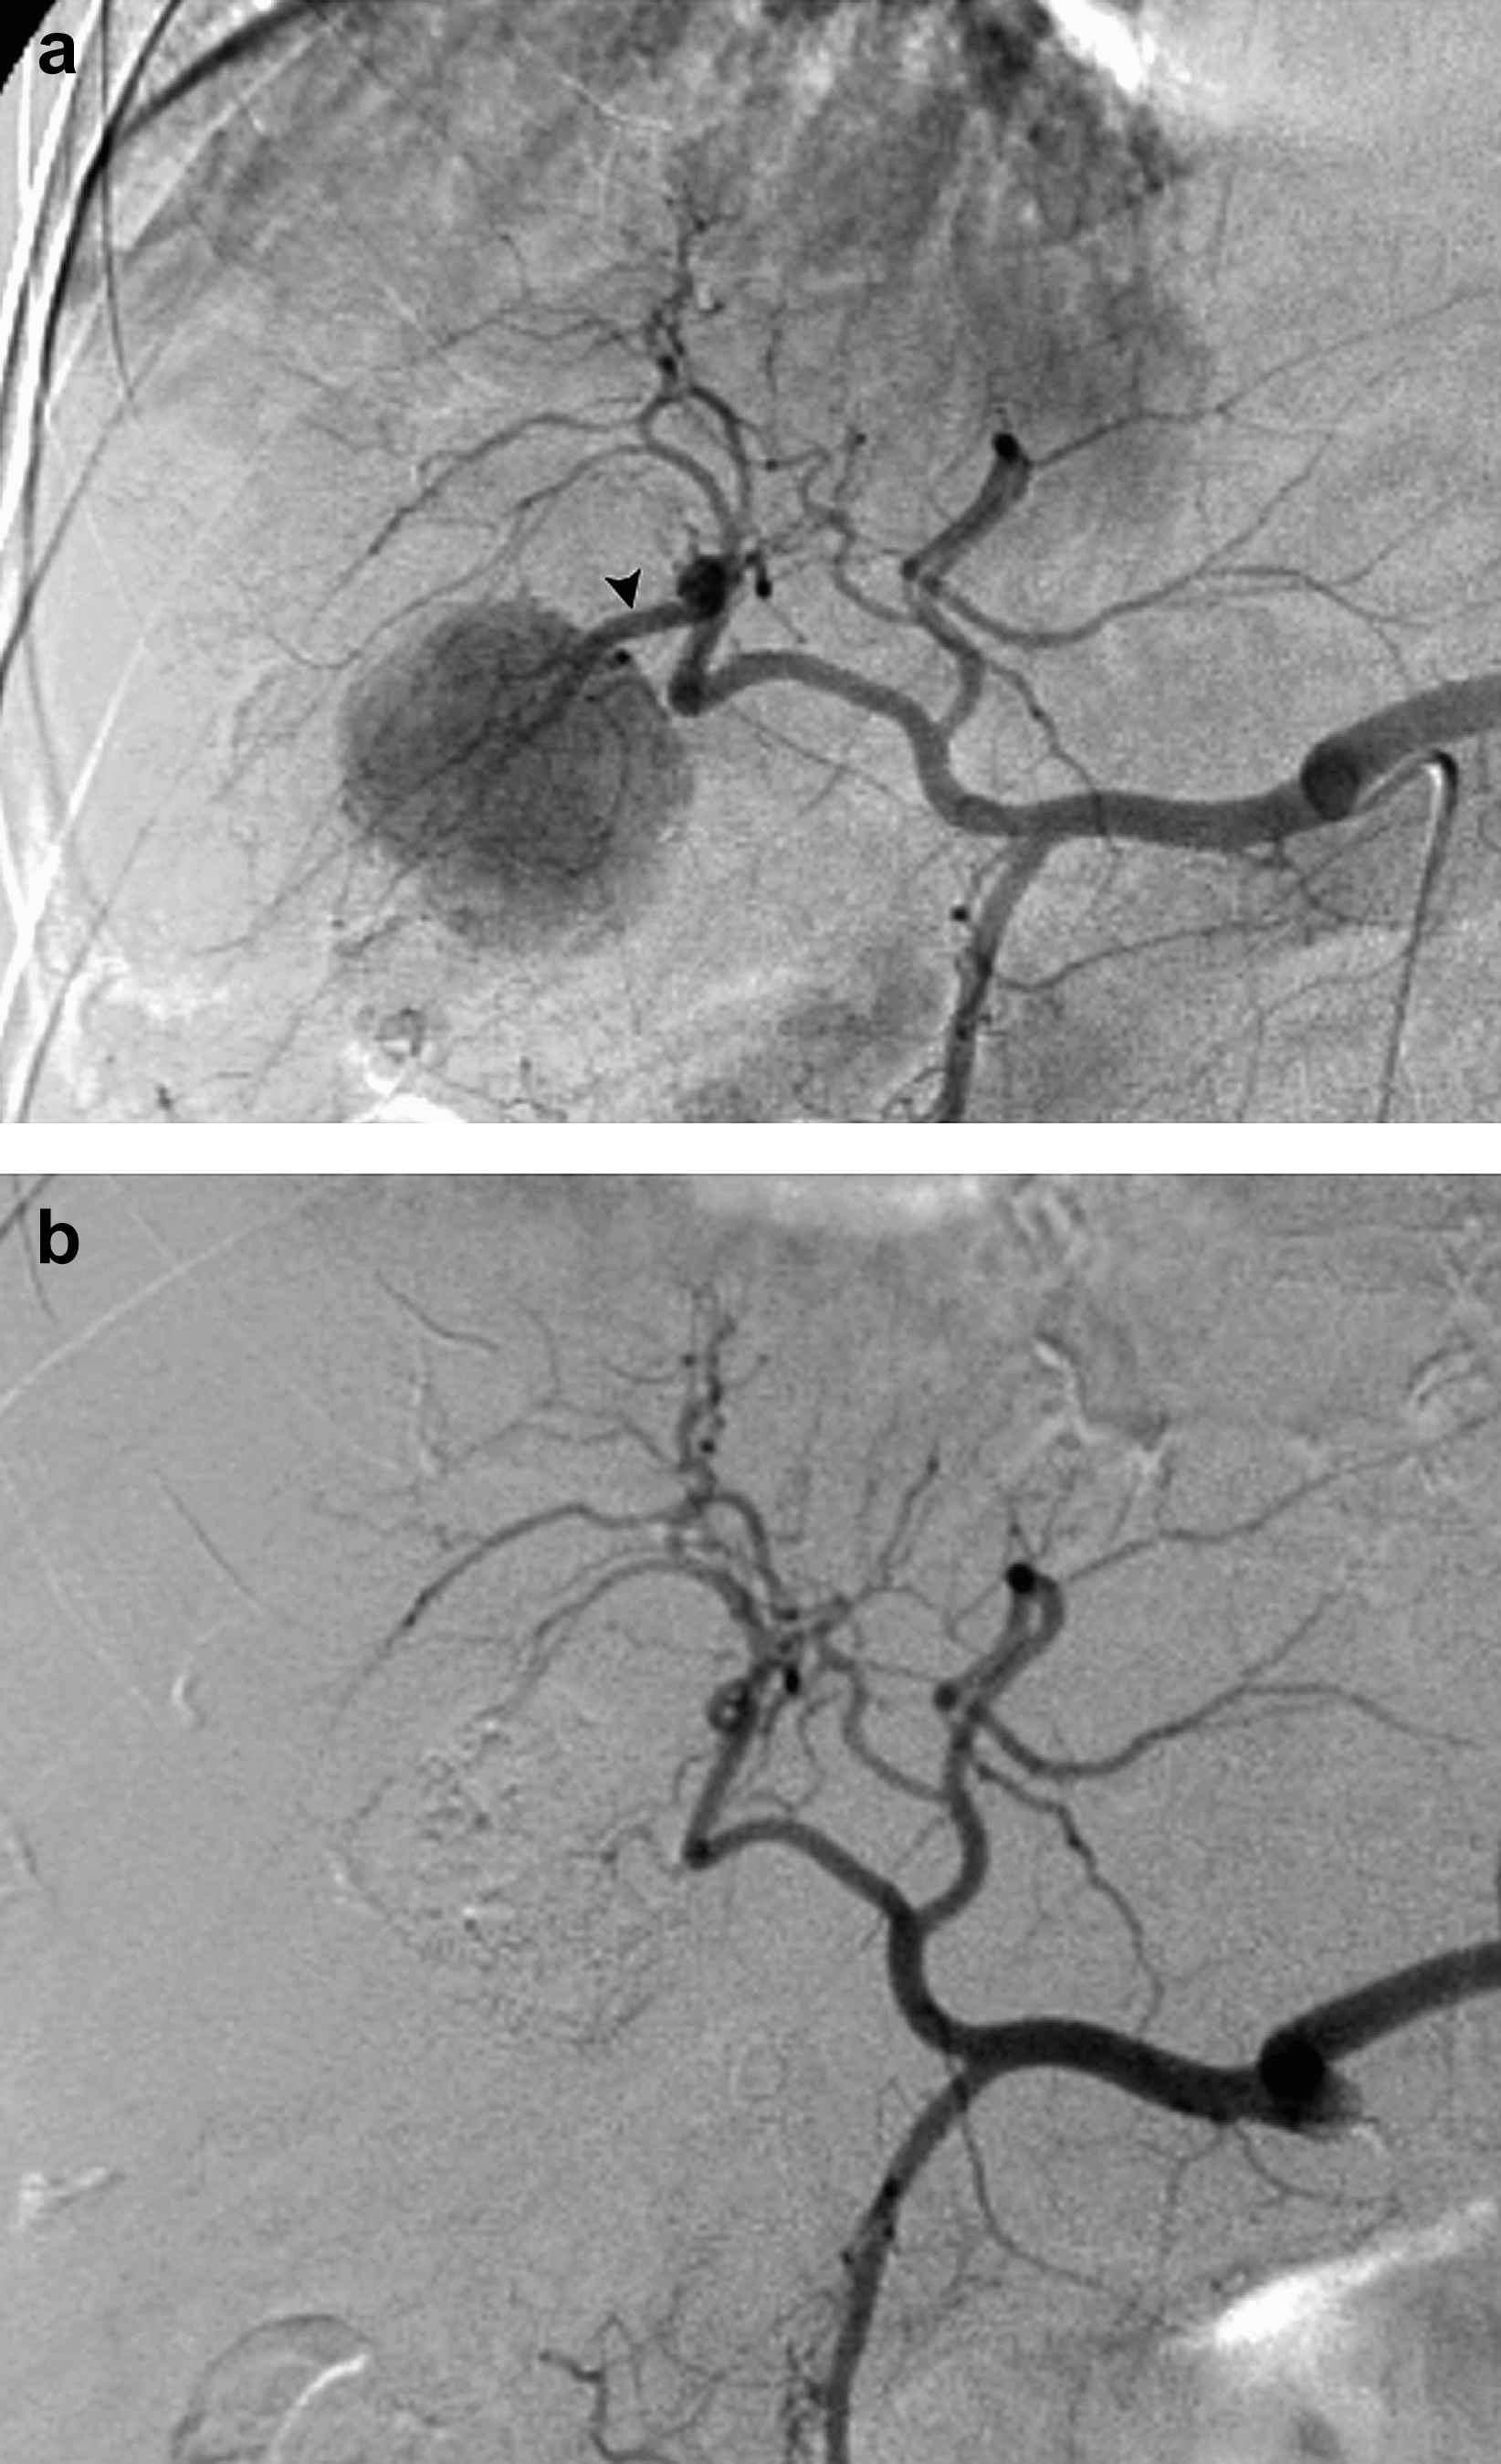

48-year-old woman with hepatitis C virus liver disease and biopsy proven unifocal HCC. Arteriogram (a) during TACE reveals hypervascular tumor supplied by segment 6 artery (arrowhead), from which selective TACE performed. Arteriogram (b) during TACE performed 279 days later for treatment of left hepatic lobe tumor demonstrates new occlusion of segment 6 vessel (arrowhead).

In 16/23 (70%) cases where vascular changes were present, repeat TACE was performed to the liver lobe with the hepatic arterial injury. In 7/23 (30%) cases, TACE was performed to the contralateral liver lobe for treatment of bilobar tumor. TACE was successfully performed in 16/16 (100%) cases where vascular changes were present and TACE was repeated to the same liver lobe. In 6/16 (38%) cases, there was no therapy limiting flow impediment from the existing vascular abnormality (Fig. 3). In 10/16 (62%) cases, TACE was performed via other ipsilateral hepatic arterial tumor feeding branch vessels. Analysis of differences in injectable chemotherapy volume between cases with and without vascular change was not possible due to lack of chemotherapy dose data.